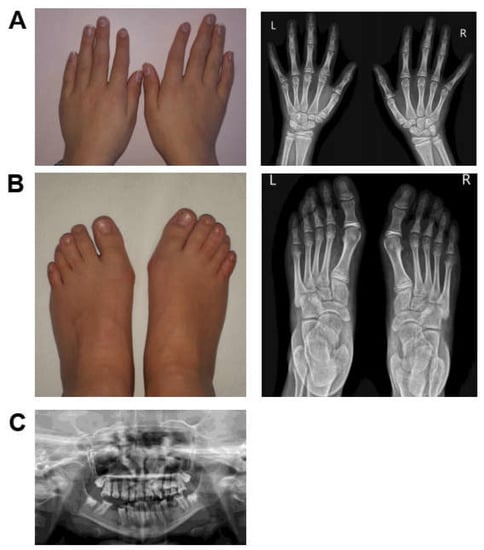

| Skeletal abnormalities | tapered fingers (HP:0001182); bilateral clinodactyly of toes (HP:0001863) | brachydactyly (HP:0001156); contractures of the hand (HP:0009473) | brachydactyly (HP:0001156) | NA | NA | - | bilateral syndactily of the fingers (HP:0010492) and toes (HP:0001770); clinodactyly (HP:0001863); broad thumb (HP:0011304) | short fifth fingers (HP:0009237); tapered distal phalanges of fingers (HP:0009884); left hand postaxial polydactyly (HP:0100259) | unilateral polydactily (HP:0010442) | NA | NA | tapered fingers (HP:0001182); hallux valgus (HP:0001822); butterfly vertebrae (HP:0003316) | 7/8 (87.5%) |